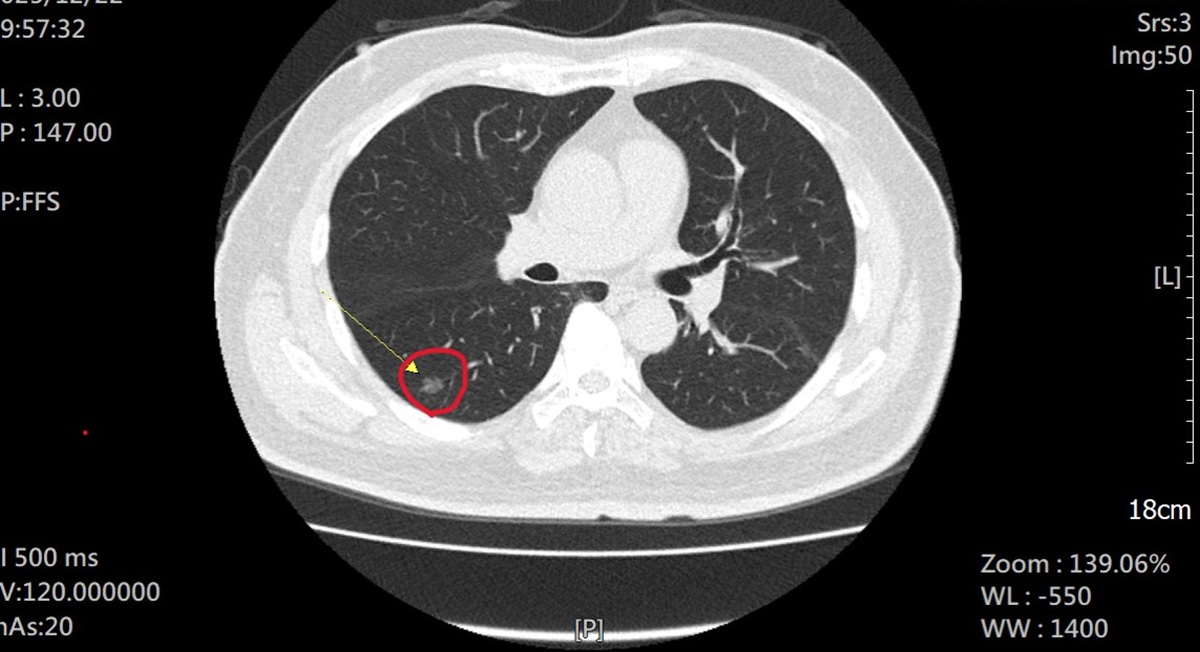

66歲陳姓男子抽菸30餘年,雖然家人一直勸他戒菸,但始終未能成功。去年年底第一個孫子誕生,他為小嬰兒不要吸二手菸,下定決心戒菸,前往員榮醫院胸腔內科主任林鴻慶醫師戒菸門診。因符合國健署肺癌補助計畫,接受「低劑量電腦斷層(LDCT)」篩檢。沒想意外揪出右下肺部有一處直徑約 1 公分的毛玻璃狀病變,疑似早期肺腺癌。

▲林主任強調,LDCT 是目前唯一能有效偵測直徑 1 公分以下細微病灶的工具。(圖/員榮醫院提供)

▲林主任強調,LDCT 是目前唯一能有效偵測直徑 1 公分以下細微病灶的工具。(圖/員榮醫院提供)

林主任強調,LDCT 是目前唯一能有效偵測直徑 1 公分以下細微病灶的工具。臨床數據顯示,第一期肺癌的五年存活率高達 90% 以上;反之,一旦延誤至第四期,存活率則驟降至約 15%。早期發現比晚期發現,患者五年存活率差 6 倍。